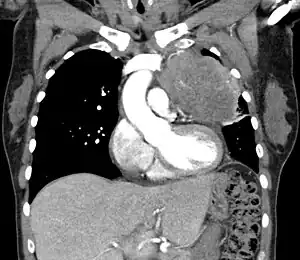

| Thymic carcinoma seen on CT. | |

Diagnosis of thymic carcinoma is based on a combination of clinical, radiologic, and biopsy findings. Most early cases are asymptomatic and found incidentally on chest radiographs as a mass in the anterior mediastinum. Further evaluation consists of additional imaging, such as CT, MRI, and PET, and tumor biopsy, which is the gold standard and provides the definitive diagnosis.[4] Biopsy may be done prior to surgery by fine needle aspiration or during the surgery with concomitant evaluation by the pathologist.[7] Other carcinomas with malignant spread to the thymus are on the differential diagnosis and must be excluded, as they may appear similar to thymic carcinoma on histopathological examination. [2]